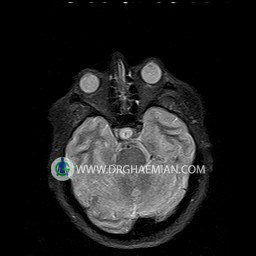

پزشکان اغلب از تصویربرداری ام آر آی برای تشخیص و درمان عارضه های پزشکی که فقط با استفاده از اشعه ایکس یا میدان مغناطیسی و امواج رادیویی قابل مشاهده است، استفاده می کنند. دستگاه ام آر آی تصاویر دقیق از ساختار های داخلی بدن ایجاد می کند. در این کیس نوریت اوربیت چب و سلای خالی بیمار مشاهده می شود.

Evaluable portions of the neurocranium and paranasal sinuses show no abnormalities .

– Small fluid around the left optic nerve with mild edema suggestive for left optic neuritis

– Extension of suprasella cistern to sella with thin pituitary gland in floor of sella ( empty sella )

are seen